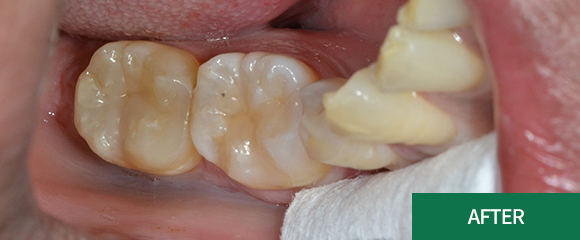

충치치료

레진

인레이

크라운